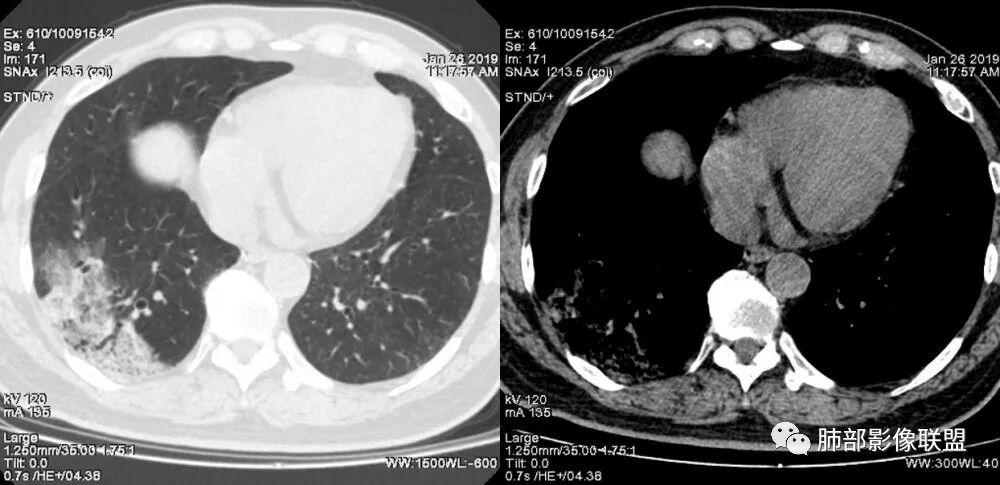

右肺下叶基底段靠胸膜实变/磨玻璃混杂密度影,边界清楚,内见多发空泡(蜂窝样趋势改变?); 临床:咳嗽咳痰,无发热、胸痛; 考虑腺癌:无发热,感染性病变不首先考虑;部分层面形态类楔形,鉴别肺栓塞

中年女性,咳嗽咳痰。右肺下叶片状高密度影,部分实性密度,周围见边界清晰磨玻璃影,内见小空泡,实性区部分支气管堵塞,有重力效应,考虑肺炎型肺癌,建议查痰脱落细胞。

老年人,右肺下叶斑片状阴影,病灶有膨胀性,边缘可见磨玻璃影,其边界清晰,内见僵硬的支气管,部分支气管扩张,首先考虑占位性病变,粘液性腺癌可能。鉴别感染性病变,后者边缘多有收缩性改变或者平直,内部支气管走形自然。

老年女性,右下肺实变影,糊墙,外朝内发展,病灶里有小叶内间质增厚,周围边界清楚了GGO,支气管扩张明显,考虑粘液癌;不符合点,支气管扩张太厉害了,鉴别淋巴瘤。

患者中年女性,咳嗽咳痰就诊。胸部CT:右肺下叶后基底段片状实变影,由胸膜向内发展呈扇形,病灶里有小叶内间质增厚、蜂窝状影,周围边界清楚GGO,内可见扩张支气管,淋巴结无明显肿大。综合符合粘液腺癌。

右肺下叶胸膜下大片状MGGO,其内结构紊乱,可见空泡征,病灶内近端支气管扩张,远端闭塞,形态不规则,边界部分清楚,部分似清非清,考虑粘液腺癌,鉴别淋巴瘤

该病灶主病灶位于胸膜下(肋膈角处),边缘膨隆改变,周围毛玻璃,边界清楚,病灶内支气管僵直,轻度扩张,小分支无,符合枯树枝改变,有多发小空泡(难与支气管区别),应该符合肺炎性肺癌,但无蜂窝,没有增强无法判断有无粘液、血管特点,如果周围显示的空泡是支气管,其已达到远端,这些有符合炎性特点,工作中,我会先抗炎膨后复查再定。

这是潘老师说的外向内吗?右下实变,蜂窝,GGO,支气管变形迂曲,局部膨胀感,肺炎性肺癌,粘液腺癌可能。常规先抗炎再复查。鉴别淋巴瘤,淋巴瘤支气管一般不变形,壁光整,病程长。

2.病灶示中央实变区,周围GGO,可见明显小叶间隔增厚,GGO边界清楚,应当考虑到恶性病变的可能性。肺炎因炎性水肿及渗出,影像上边界常模糊不清,注意早期粘液腺癌可出现似清非清的边界。粘液腺癌因粘液成份较多,密度一般偏低,纵隔窗病灶常会消隐或范围会明显缩小,这不同于炎性实变。

3.病灶内支气管走形略显僵直,侧支少(粘液阻塞),也符合肺腺癌的枯树枝征。而大叶性肺炎的支气管是管壁光整、通畅、自然,结核的支气管常常壁增厚,甚至狭窄后扩张;